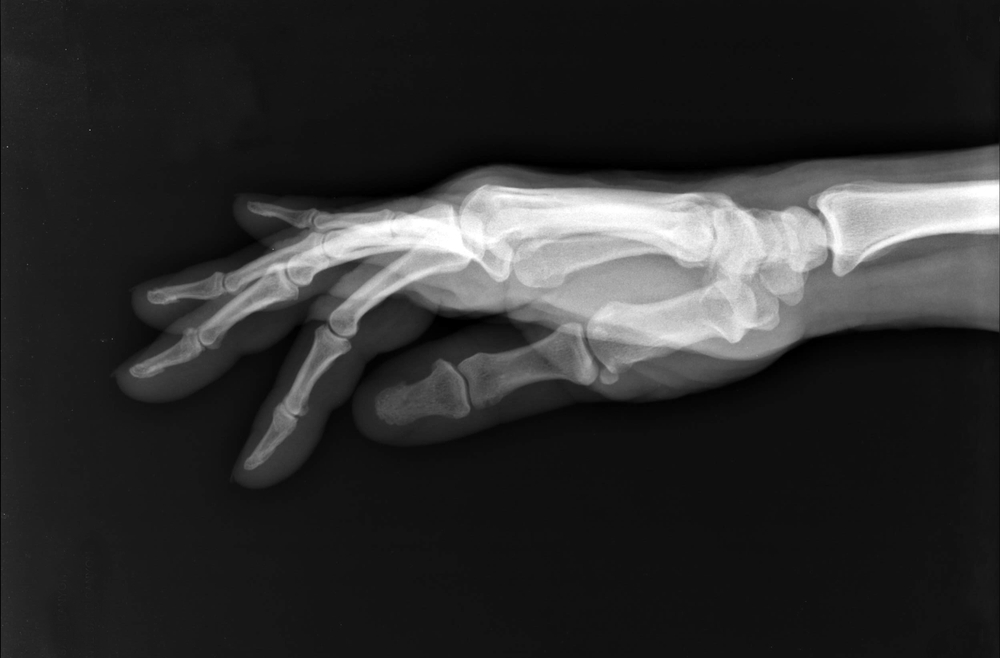

Thumb Arthritis Treatment — How Physiotherapy Can Help

by North 49 Physiotherapy | Oct 31, 2025 | hand therapy, Physiotherapy, Uncategorized

If you’ve noticed pain, stiffness, or weakness in your thumb when trying to open jars, turn keys, or even use your phone, you’re not alone. Arthritis in the thumb is a common condition that can make everyday tasks surprisingly difficult. The good news is that with the...